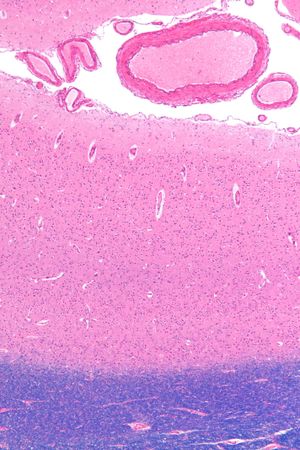

대뇌 피질은 뇌의 가장 바깥쪽 층으로, 주름진 구조를 가지며, 인지, 감각, 운동 기능을 담당하는 부위이다. 해부학적으로 이랑과 고랑으로 구분되며, 전두엽, 두정엽, 측두엽, 후두엽, 섬엽, 변연엽으로 나뉜다. 대뇌 피질은 6개의 층으로 이루어진 신피질과 3~4개의 층을 가진 구피질로 구성되며, 각 층은 특정한 신경세포와 연결을 가진다. 대뇌 피질의 발달은 태아기부터 시작되며, 유전자와 환경의 상호작용에 의해 영향을 받는다. 뇌졸중, 뇌전증, 알츠하이머병, 발달 장애 등 다양한 질환과 관련이 있으며, 뇌 기능 매핑 및 유전자 변이 연구를 통해 질병 진단 및 치료에 활용된다.

대뇌 피질은 뇌의 표면을 덮고 있는 신경 세포의 집합으로, 주름진 형태를 통해 표면적을 넓혀 더 많은 신경 세포를 수용한다. 대뇌 피질은 대뇌 반구 표면의 바깥 덮개이며, 이랑이라고 불리는 봉우리와 고랑이라고 불리는 홈으로 접혀 있다. 사람의 뇌에서 두께는 2mm~4mm이며,[6] 뇌 질량의 40%를 차지한다.[7] 대뇌 피질의 90%는 6층의 신피질이며, 나머지 10%는 3~4층의 구피질로 구성되어 있다.[7] 피질에는 140억~160억 개의 뉴런이 있다.[7]

대뇌 피질은 크게 6개의 층으로 구성된 신피질과 3~4개의 층으로 구성된 구피질로 나뉜다. 신피질은 대뇌 피질의 대부분(약 90%)을 차지하며, 각 층은 신경 세포의 종류와 연결 방식에서 차이를 보인다.[7] 이러한 층 구조는 대뇌 피질의 기능을 이해하는 데 중요한 역할을 한다.

사람의 뇌에서 대뇌 피질은 2~4mm의 두께를 가지며,[6] 뇌 질량의 40%를 차지한다.[7] 피질에는 140억~160억 개의 뉴런이 존재하며,[7] 이 뉴런들은 피질 기둥과 피질 미니 기둥 형태로 배열되어 있다.[8][9]

대뇌 피질의 대부분 영역('''신피질''', 동종피질)에서는 신경 세포가 규칙적인 6층 구조를 이루며 정연하게 배열되어 있다. 이 6층은 바깥쪽부터 차례로 분자층, 외과립층, 외추체세포층, 내과립층, 내추체세포층(신경세포층), 다형세포층이라고 불린다.